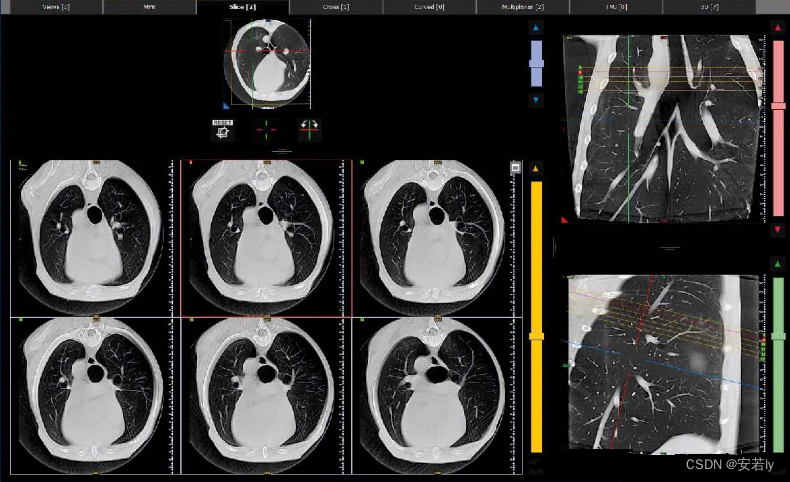

NNT软件的先进功能可以覆盖多个医学专业,特殊的重建窗口响应每个部门的不同需求。所有检查都完全兼容 DICOM 格式:它们可以通过 NNT 查看器共享或以 1:1 的比例打印。与 NewTom 采用的现代系统的出色连接性和集成性。工作流程、临床和诊断活动变得更加容易和高效。简单的 3D 显示界面使与宠物主人的交流变得更加容易,即使是不熟悉影像阅读的观众也能清楚地了解患者的病情。可以选择软组织和骨组织的单独或叠加成像。3D 测量、气道模拟和切片工具也可用于获取感兴趣体积的横截面。用于研究牙弓的专用界面可生成横截面和轴向重建,并通过多平面重建生成与牙科全景图相当的图像。它还可以为冠状面和矢状面生成特定的重建。对于所有这些图像,可以独立管理厚度、亮度和对比度。NNT 软件有一个专门的窗口,用于骨骼结构的双边成像,例如颞下颌关节和较小的关节。观察窗在中间显示轴向图像,左侧和右侧显示专用重建;在底部中央区域,显示了 3D 效果图。